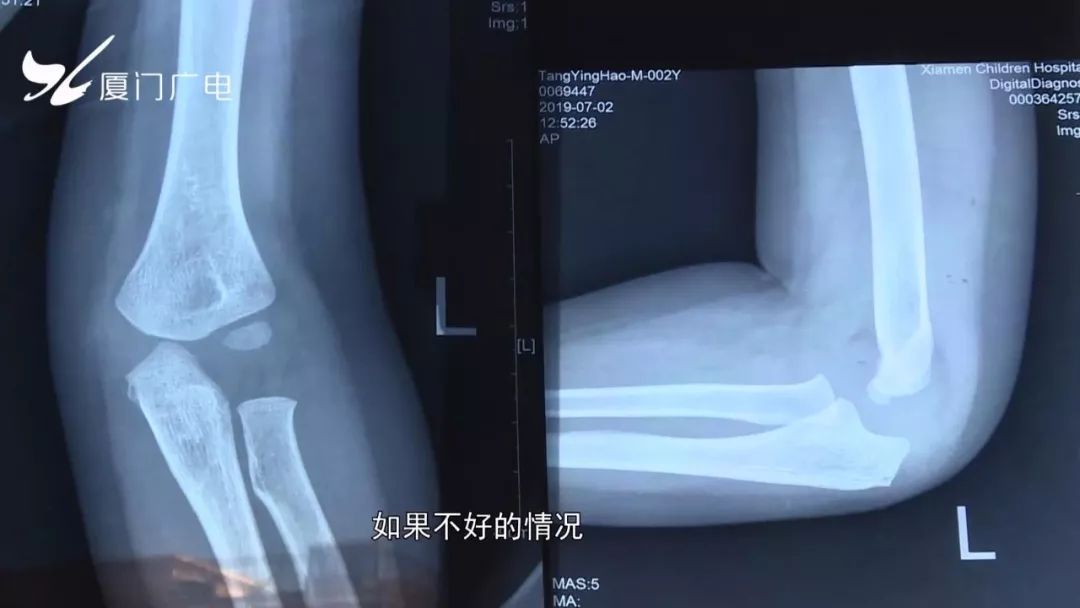

骨折了就先打石膏处理,如果发展的好的话,至少要一个月才能拆石膏,拆